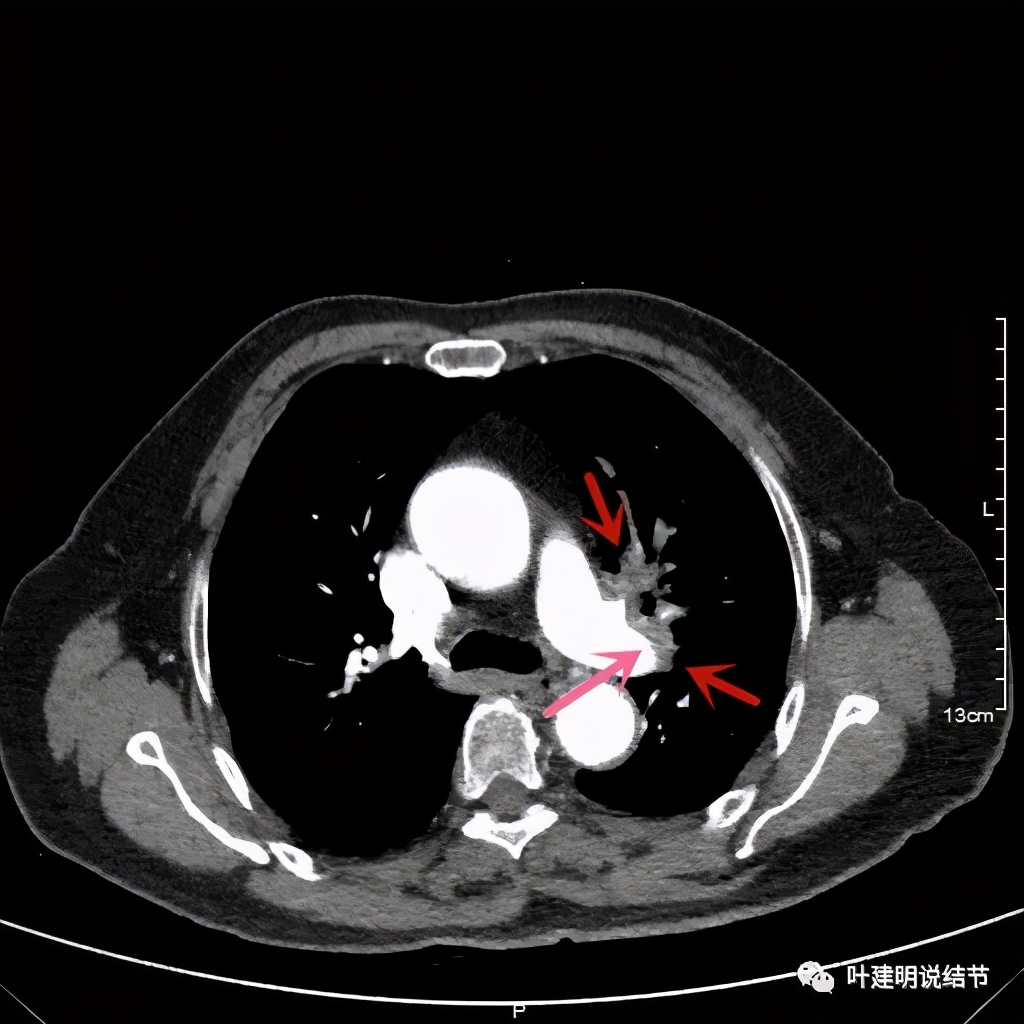

上图桔色箭头示左肺动脉分支处仍被软组织(原肿瘤所在)包绕,粉色箭头示肺动脉仍与肿瘤处关系密切

上图也示桔色箭头示左肺动脉分支处仍被软组织(原肿瘤所在)包绕,粉色箭头示肺动脉仍与肿瘤处关系密切